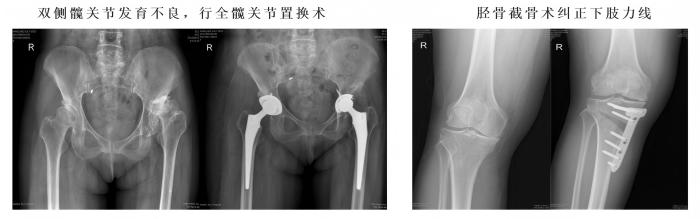

1、常规完成复杂全髋、膝关节置换手术(水泥型、生物型)、单髁置换手术、胫骨高位截骨手术、复杂保髋手术、股骨头坏死综合治疗、高龄老人髋部骨折综合治疗。

四、小儿骨科医学组:为了造福广大患儿,三院骨科特别引进小儿骨科专家张春辉主任,(我市仅有的两位专业小儿骨科专家之一)。先后开展儿童先天性髋关节发育不良、儿童骨折、骨骺损伤、发育畸形等各种疾病的手法修复和手术修复,治疗效果满意。